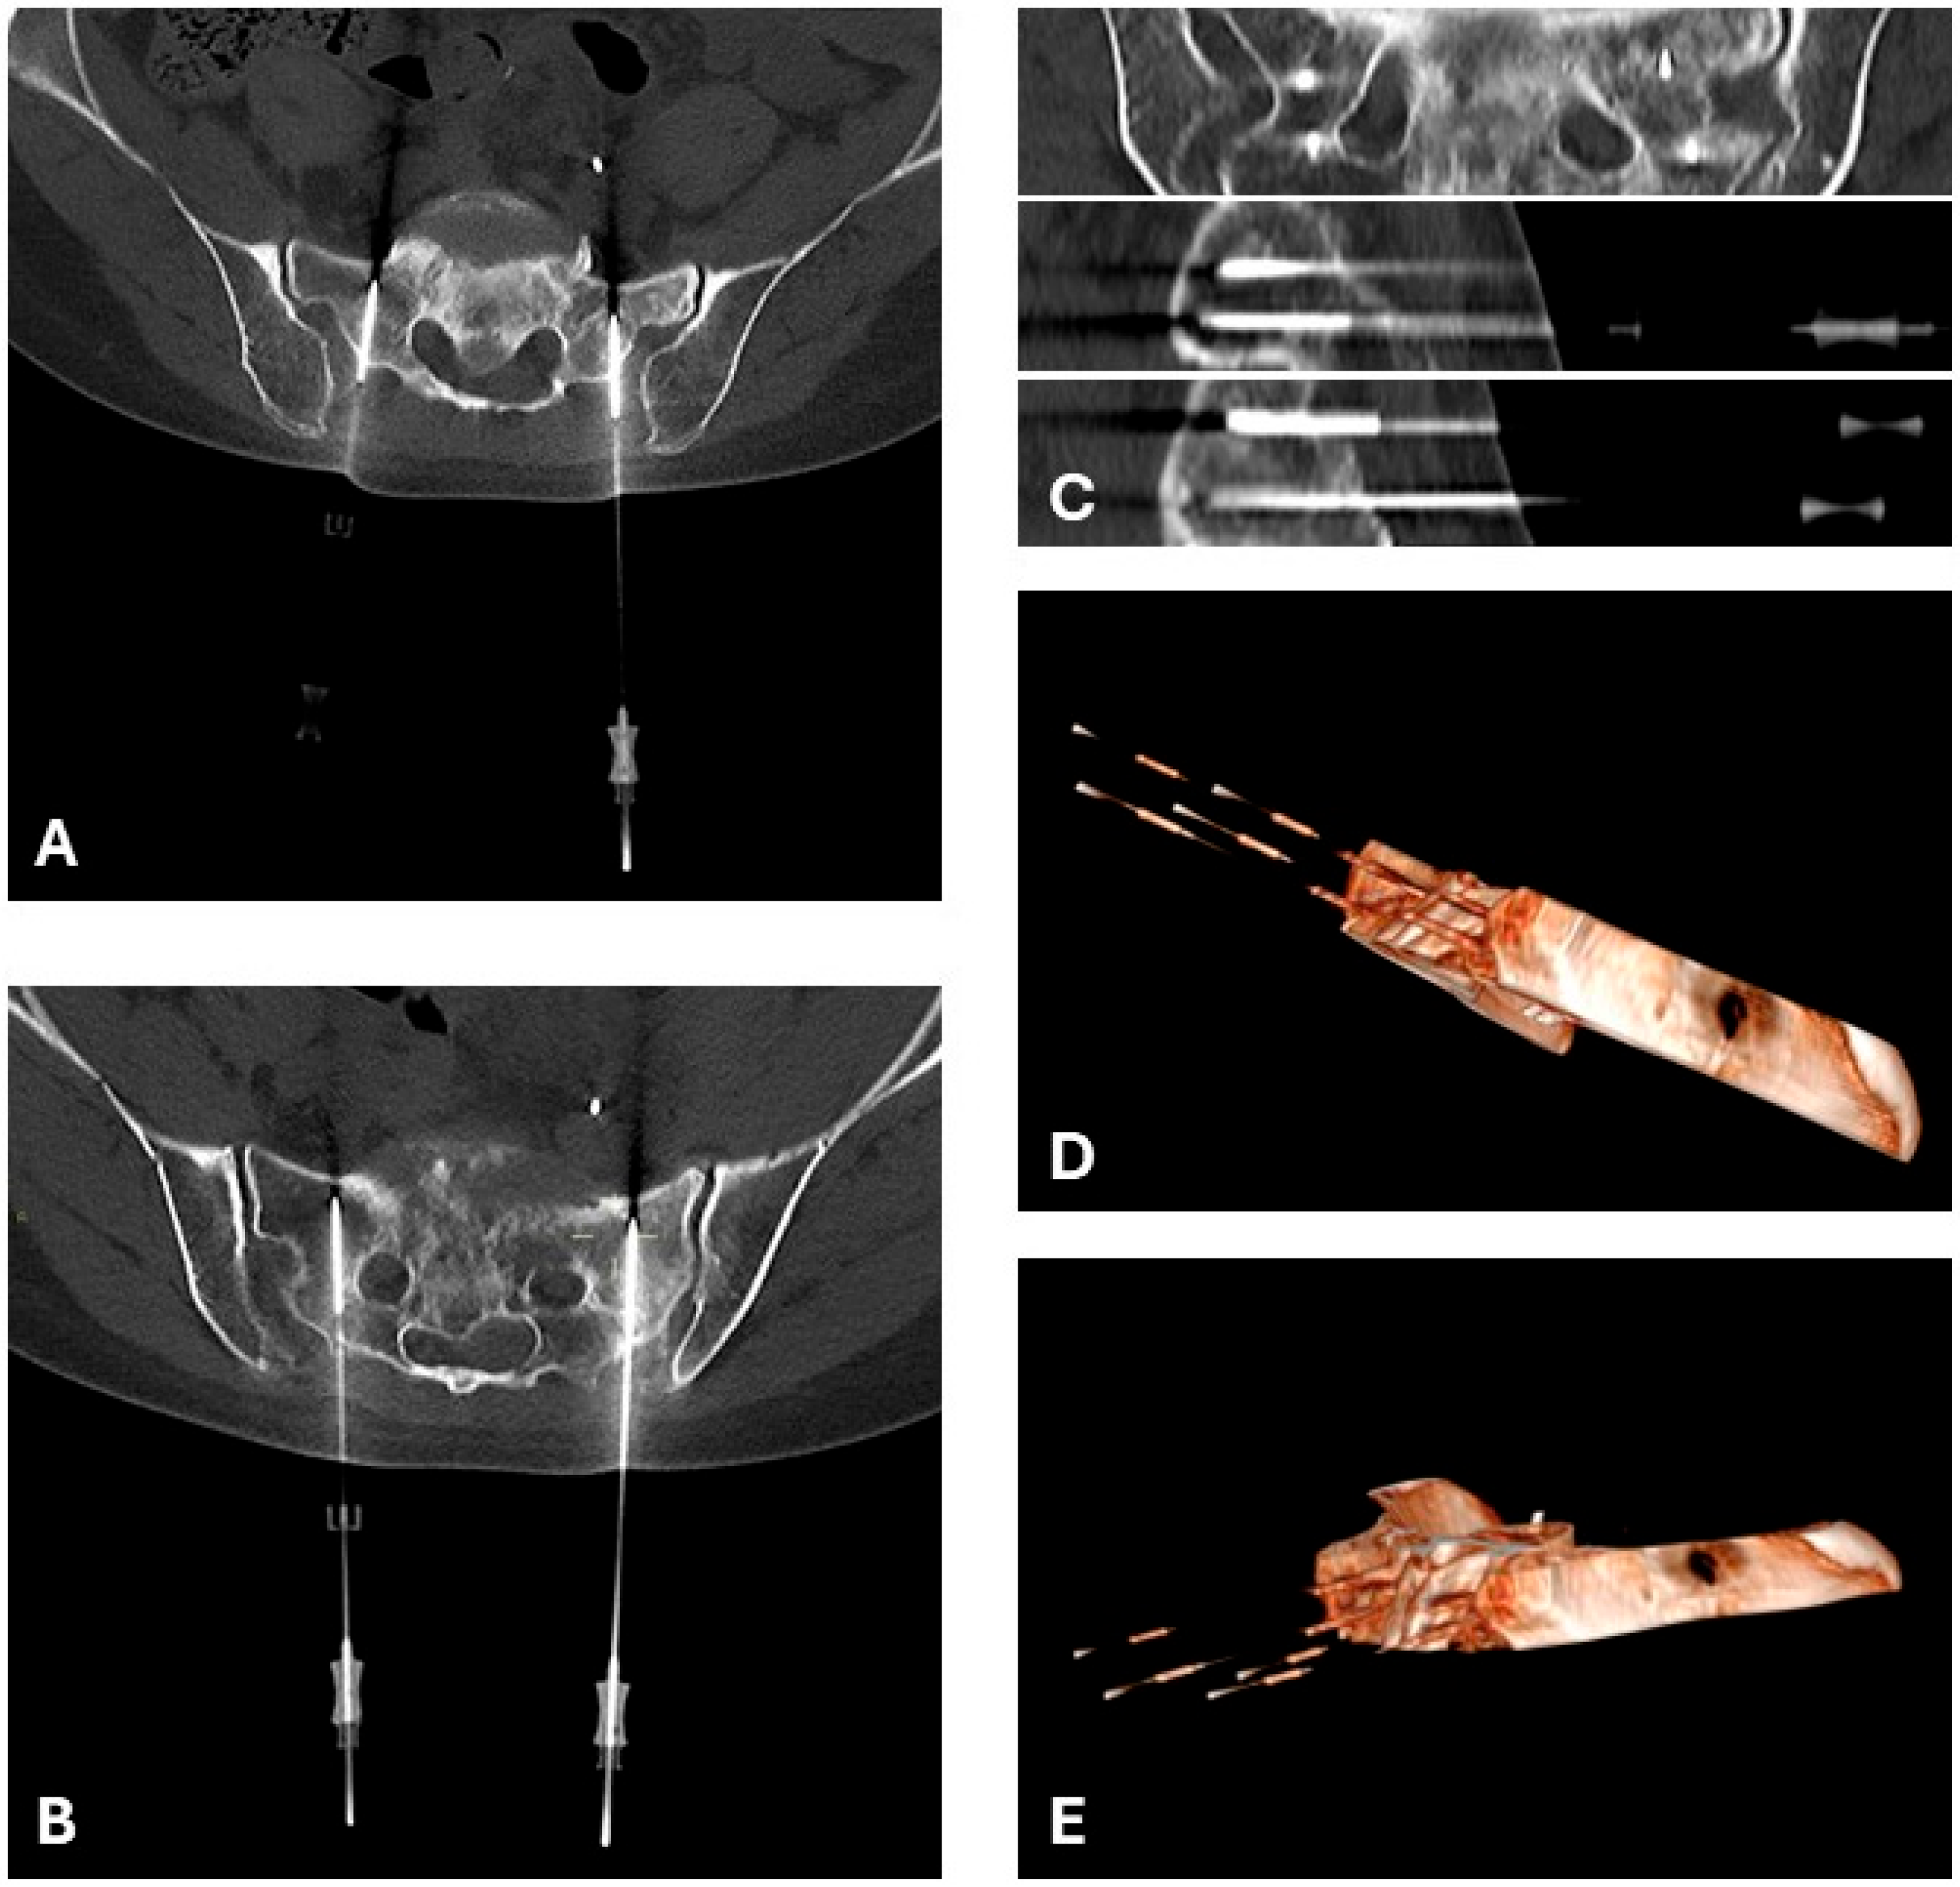

2.4. Image Guidance and Navigation

4.1. Spinal Metastases and Spinal Epidural Invasion

- Cindrič, H.; Miklavčič, D.; Cornelis, F.H.; Kos, B. Optimization of transpedicular electrode insertion for electroporation-based treatments of vertebral tumors. Cancers 2022, 14, 5412. [Google Scholar] [CrossRef]

- Cindrič, H.; Kos, B.; Tedesco, G.; Cadossi, M.; Gasbarrini, A.; Miklavčič, D. Electrochemotherapy of spinal metastases using transpedicular approach—A numerical feasibility study. Technol. Cancer Res. Treat. 2018, 17, 1–13. [Google Scholar] [CrossRef]

| 2024 | Angelini [18] | 3 | Case Series | Spinal | Transpedicular needle electrodes during surgery + IV bleomycin. | Pain relief and neurologic improvement; stable disease on imaging |